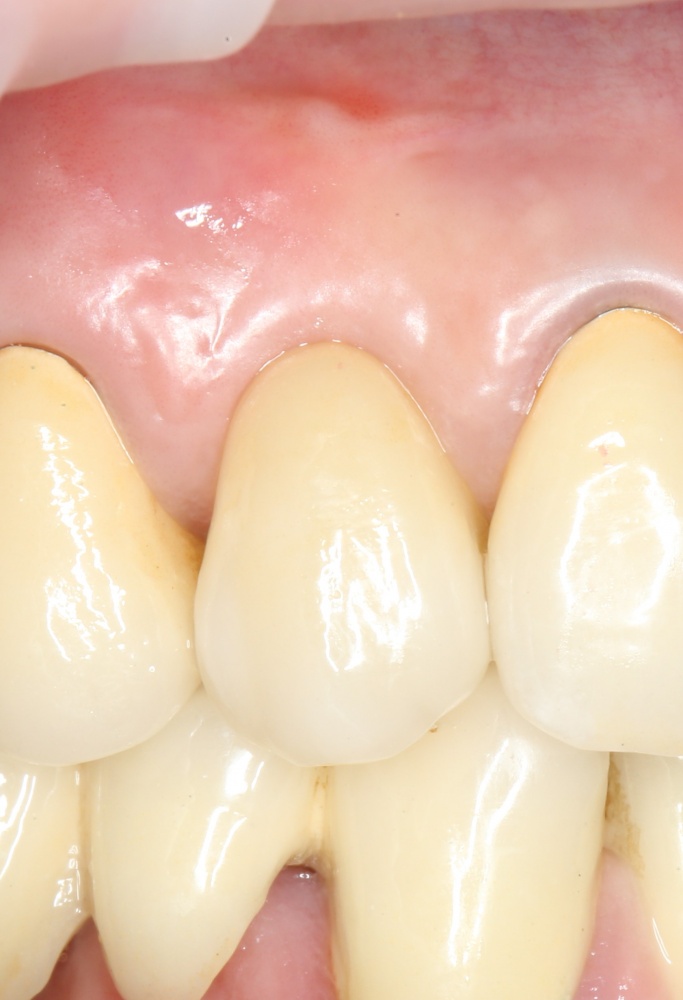

Рекомендации по установке имплантов. Для всех. Часть II.